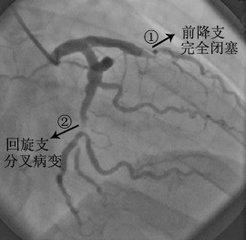

4. la coronarographie :

Enfin, il est temps de parler du roi des examens cardio-vasculaires. La coronarographie est bien plus ancienne que moi : depuis 1959, date de la première coronarographie réalisée par le Dr Sones du Centre médical de Cleveland aux États-Unis, l'histoire de la coronarographie remonte à près de 56 ans. Depuis sa création, la coronarographie est devenue l'étalon-or de la maladie coronarienne en raison de ses caractéristiques intuitives et objectives.

La signification de l'indice d'or pour le diagnostic de la maladie coronarienne est un peu comme le testament de l'empereur, qui dit oui ou non. Quels que soient les examens effectués sur les artères coronaires, dès lors qu'une coronarographie a été réalisée, tout dépend des résultats de la coronarographie. La coronarographie consiste à insérer un cathéter épais à cœur de stylo à bille dans l'artère fémorale ou l'artère radiale, à le placer dans l'ouverture de l'artère coronaire et, grâce à l'injection d'un produit de contraste et au développement de l'image, à observer l'alignement, le nombre et la déformation des vaisseaux de l'artère coronaire sous le produit de contraste ; à évaluer l'existence, la gravité et l'étendue des lésions de l'artère coronaire ; à évaluer les changements fonctionnels des artères coronaires, y compris le spasme des artères coronaires et la présence ou l'absence de circulation dans les branches latérales ; en même temps, elle peut également prendre en compte le côté gauche de l'artère coronaire et évaluer les changements fonctionnels des artères coronaires. Évaluation des modifications fonctionnelles des artères coronaires, y compris le spasme des artères coronaires et la circulation des branches latérales ; en même temps, elle peut prendre en compte l'évaluation de la fonction cardiaque gauche. On peut dire que cet examen couvre fondamentalement tous les examens liés au cœur, à l'exception de l'électrophysiologie.

Les risques de la coronarographie se concentrent sur : (1) l'intrusion de la plaque artérielle pendant la ponction, qui peut conduire au délogement de la plaque coronaire et au spasme coronaire ; (2) l'hématome post-procédure au point de ponction ; et (3) l'effet du produit de contraste sur la fonction rénale. Il convient de noter que ces risques, bien que présents, peuvent être évités par une évaluation vasculaire préopératoire, une compression postopératoire adéquate pour l'hémostase et une hydratation suffisante.

En conclusion, si elle est réalisée par un interventionniste et une équipe expérimentés, la sécurité de la coronarographie est encore largement garantie et il n'y a pas lieu de s'inquiéter outre mesure. Les avantages de la coronarographie l'emportent sur ses inconvénients par rapport à l'utilité diagnostique pour les patients atteints d'une maladie coronarienne.

2, la coronarographie : il s'agit d'un examen invasif, par ponction artérielle, le cathéter est introduit dans l'ouverture de l'artère coronaire, l'agent de contraste y est injecté et la situation de remplissage à l'intérieur du vaisseau sanguin et la vitesse du flux sanguin sont observées aux rayons X ; ce type d'examen permet de voir directement la situation à l'intérieur du vaisseau sanguin, c'est donc l'indice d'or pour le diagnostic de la maladie coronarienne, mais l'inconvénient est qu'il s'agit d'un examen invasif ;

6. coronarographie (coronarographie transartérielle percutanée)La procédure. Elle consiste en une ponction artérielle (artère radiale au poignet ou artère fémorale à la base de la cuisse) pour amener un cathéter jusqu'à l'orifice de l'artère coronaire, injecter un produit de contraste iodé pour observer la morphologie de l'artère coronaire et le flux sanguin, et diagnostiquer généralement une maladie coronaire avec une sténose de plus de 50 %. Cette méthode est actuellement "l'étalon-or" pour le diagnostic de la maladie coronarienne. Elle a l'avantage d'être précise (bien sûr, il existe des cas d'imprécision, dus à l'angle de projection, à l'expérience du médecin, à la déformation du vaisseau, etc.), et de pouvoir être traitée immédiatement après la détection du problème, en utilisant la dilatation par ballonnet ou le stenting (et d'autres techniques) pour ouvrir l'artère coronaire et améliorer l'apport sanguin, et pour détecter et traiter le problème dans le même temps. Cette méthode est une procédure peu invasive dont la technologie a fait ses preuves et dont la sécurité est excellente. Mais comme il s'agit d'une procédure, il y a des blessures, des risques et le même problème avec les produits de contraste.

- La coronarographie est une technique de pointe en matière de plomberie.Le principe de la coronarographie est similaire à celui de l'angiographie coronaire, mais la coronarographie est un examen invasif au cours duquel un tube est envoyé par une artère de la main ou de la cuisse jusqu'aux artères coronaires du cœur, où un agent de contraste est injecté directement dans les artères coronaires, et la morphologie des artères coronaires est visualisée sur une caméra de film (DSA).Ce test est l'étalon-or pour le diagnostic de la maladie coronarienne, et il est capable de voir non seulement le tronc principal et les grandes branches des artères coronaires, mais aussi certaines des branches plus petites. On dit qu'il s'agit d'un plombier avancé, surtout parce qu'il peut être utilisé non seulement pour diagnostiquer la maladie coronarienne, mais aussi pour délivrer des ballons ou des stents, etc. à travers ce cathéter en vue d'un traitement, ce qui est connu sous le nom de thérapie interventionnelle coronarienne.

coronarographie

La coronarographie reste l'examen de référence pour le diagnostic clinique de la maladie coronarienne, mais elle présente l'inconvénient de nécessiter l'utilisation de produits de contraste et de procédures interventionnelles invasives. Pour évaluer le degré de sténose des artères coronaires, la coronarographie peut évaluer les changements fonctionnels des artères coronaires, y compris le spasme des artères coronaires et la présence ou l'absence de circulation collatérale ; en même temps, elle peut également prendre en compte l'évaluation de la fonction du cœur gauche et ainsi de suite. S'il est confirmé qu'un stent peut être placé dans la zone infarcie pour reconstruire le flux sanguin, un stent doit être implanté directement pour ouvrir le flux sanguin dès que possible, afin de minimiser les dommages myocardiques provoqués par l'infarctus aigu.

La coronarographie est actuellement l'examen de référence pour le diagnostic des maladies coronariennes. Le cathéter est inséré dans l'ouverture de l'artère coronaire et une petite quantité de produit de contraste est injectée pour montrer le flux sanguin de l'artère coronaire, pour observer de manière dynamique le flux sanguin de l'artère coronaire et la situation anatomique, pour comprendre la nature, la localisation, l'étendue et le degré des lésions de l'artère coronaire, et pour observer les artères coronaires à la recherche de malformations, de calcifications et de la formation d'une circulation collatérale.

4. la coronarographie : c'est l'"étalon-or" pour le diagnostic de la maladie coronarienne. Elle permet de déterminer si les artères coronaires sont rétrécies ou non, le degré, l'étendue et la localisation du rétrécissement, etc. et d'orienter les mesures à prendre pour le traitement. Parallèlement, la ventriculographie gauche permet d'évaluer la fonction cardiaque.